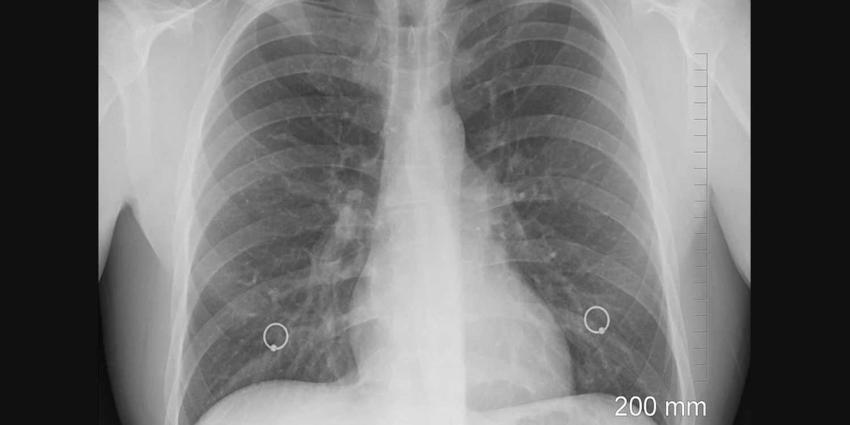

Het aantal mensen met tuberculose (tbcTuberculose) in Nederland is in 2021 iets toegenomen. In 2021 waren er 680 tbc-patiënten in Nederland. Dit is 9 procent meer dan in 2020 (622 patiënten). Bij 296 patiënten bevond de tuberculose zich buiten de longen.

Er waren 384 patiënten met tbc in de longen. Hiervan hadden 141 open tuberculose, de meest besmettelijke vorm. Dit blijkt uit de kerncijfers van het Rijksinstituut voor Volksgezondheid en Milieu (RIVM).

Tuberculose is een infectieziekte die wordt veroorzaakt door een bacterie. De ziekte is meldingsplichtig. Dit betekent dat artsen de ziekte moeten melden aan de GGDGemeentelijke Gezondheidsdienst. De GGD meldt dit vervolgens aan het RIVM. Tuberculose kan besmettelijk zijn, bijvoorbeeld als de ziekte in de longen zit.